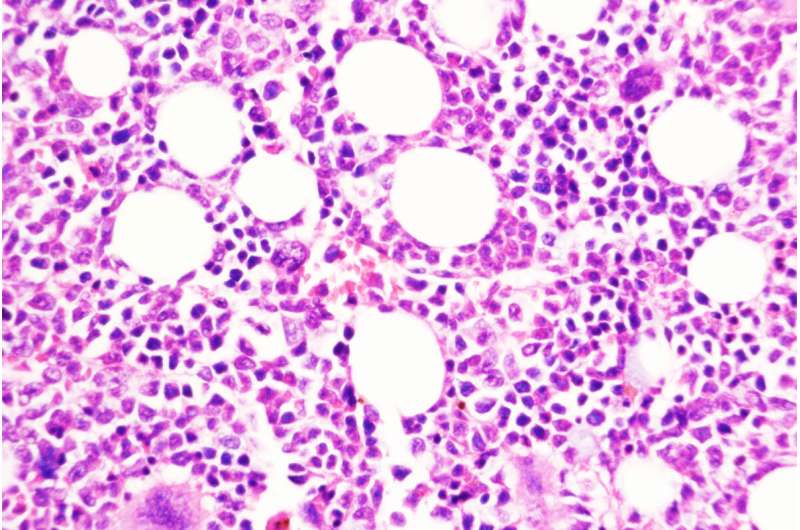

圣路易斯華盛頓大學(xué)醫(yī)學(xué)院的一項(xiàng)研究提出了一種預(yù)防慢性、生長(zhǎng)緩慢的血癌發(fā)展為侵襲性白血病的策略。圖中顯示的是用一種化合物阻斷DUSP6的小鼠骨髓,DUSP6是由慢性疾病轉(zhuǎn)變?yōu)榍忠u性疾病的關(guān)鍵分子。

使用遺傳技術(shù)刪除DUSP6基因可以防止這種癌癥模型小鼠向侵襲性疾病的轉(zhuǎn)變。研究人員還測(cè)試了一種抑制DUSP6的藥物化合物,并發(fā)現(xiàn)這種化合物(僅用于動(dòng)物研究)在兩種不同的癌癥小鼠模型和從患者身上取樣的人類腫瘤小鼠中阻止了慢性疾病向侵襲性疾病的進(jìn)展。在這些模型中,通過基因和藥物降低DUSP6水平也能減少炎癥。